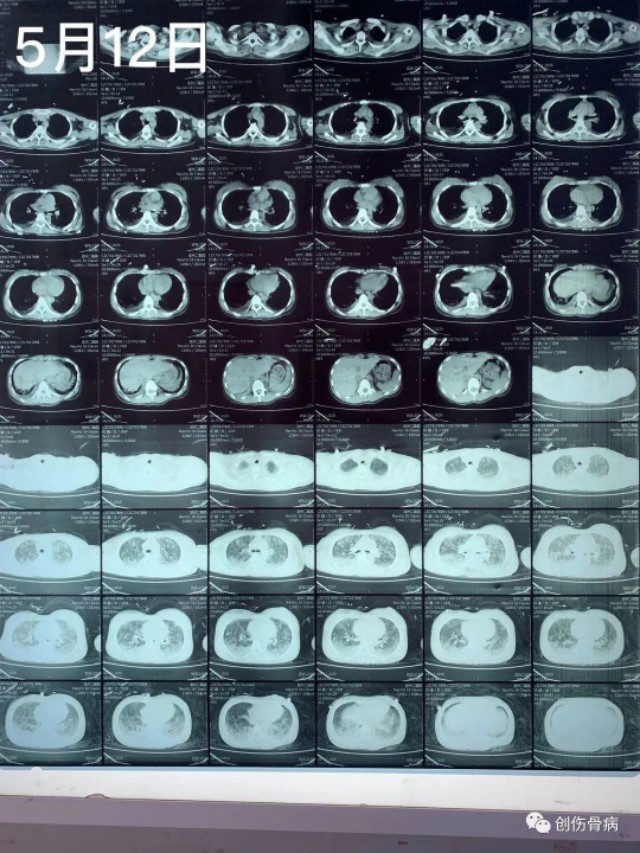

都说车祸无情,但是创伤后的并发症也依旧无情。2020年5月9日21时55分我科室接收一名18岁外伤小妹妹,当天晚上小妹妹跟爸爸妈妈路边散步被一汽车撞倒受伤,送至我院时就是一单纯右胫腓骨下段粉碎性骨折伴头皮裂伤,入院行右小腿DR及胸部CT示:2020年5月12日14时左右,小妹妹突然出现呼吸困难、烦躁不安,氧饱和度40-50%,家属诉小女孩昨日夜间有偷偷咳嗽的表现,当班医生一看就考虑脂肪栓塞立即给与安排行胸部CT示:

2020年5月12日14时左右,小妹妹突然出现呼吸困难、烦躁不安,氧饱和度40-50%,家属诉小女孩昨日夜间有偷偷咳嗽的表现,当班医生一看就考虑脂肪栓塞立即给与安排行胸部CT示:随后转入ICU气管插管、呼吸机控制呼吸、激素冲击、抗炎、脑康复等抢救治疗,短时间内出现急性肺水肿,气管插管内全是粉红色泡沫痰,恰逢月经期,各种用药都存在矛盾,血色素也直线降落,针对此类病人外界压力也挺大的,有说希望渺茫的,有说必死无疑的,也有建议转院治疗的。。。。。好在家属比较理解也比较信任我们,给予对症抢救治疗4天、13天后复查胸部CT示: